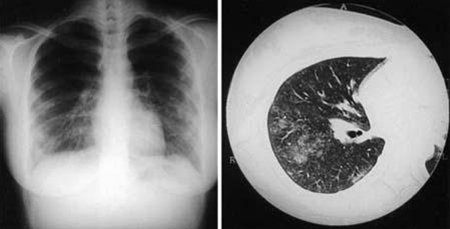

radiografia torácica

Exame

Esta pode ser exigida em infecção focalizada persistente e aguda, caso haja suspeita de complicações pulmonares.

Os achados podem variar de opacidades normais a múltiplas inespecíficas (sem um padrão ou distribuição aparente) em ambos os pulmões, mais consistentes com uma pneumonia atípica. As anormalidades mais comuns na radiografia torácica são as opacidades lobares ou segmentares. A principal característica da pneumonia por febre Q é um achado de várias opacidades arredondadas, mas isso é incomum.[37]

Podem ser observados derrame pleural, atelectasia e adenopatia hilar, mas são raros.

No contexto da infecção focalizada persistente, a radiografia torácica pode identificar duas infecções focalizadas persistentes diferentes: fibrose intersticial e pseudotumor pulmonar.[Figure caption and citation for the preceding image starts]: Pneumonia por Coxiella burnetii. Radiografia torácica e tomografia computadorizada (TC) de uma mulher de 21 anos de idade com pneumonia por Coxiella burnetii; a radiografia torácica exibe múltiplas áreas de condensação suave bilaterais nos campos pulmonares médios e inferiores; a tomografia computadorizada (TC) exibe nódulos centrolobulares pouco definidos e consolidação do espaço aéreoOkimoto N, et al. Respirology. 2004;9:278-282; used with permission of John Wiley & Sons Ltd [Citation ends].

tomografia computadorizada (TC) do tórax

Tipicamente, não é solicitada como rotina, mas pode ser usada para avaliar complicações pulmonares na doença aguda.[Figure caption and citation for the preceding image starts]: Pneumonia por Coxiella burnetii. Radiografia torácica e tomografia computadorizada (TC) de uma mulher de 21 anos de idade com pneumonia por Coxiella burnetii; a radiografia torácica exibe múltiplas áreas de condensação suave bilaterais nos campos pulmonares médios e inferiores; a tomografia computadorizada (TC) exibe nódulos centrolobulares pouco definidos e consolidação do espaço aéreoOkimoto N, et al. Respirology. 2004;9:278-282; used with permission of John Wiley & Sons Ltd [Citation ends].